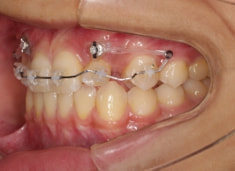

治療法:上顎急速拡大装置+クリアスナップ+フェイスマスク+上顎3番は開窓牽引CT写真にて位置確認

治療開始時